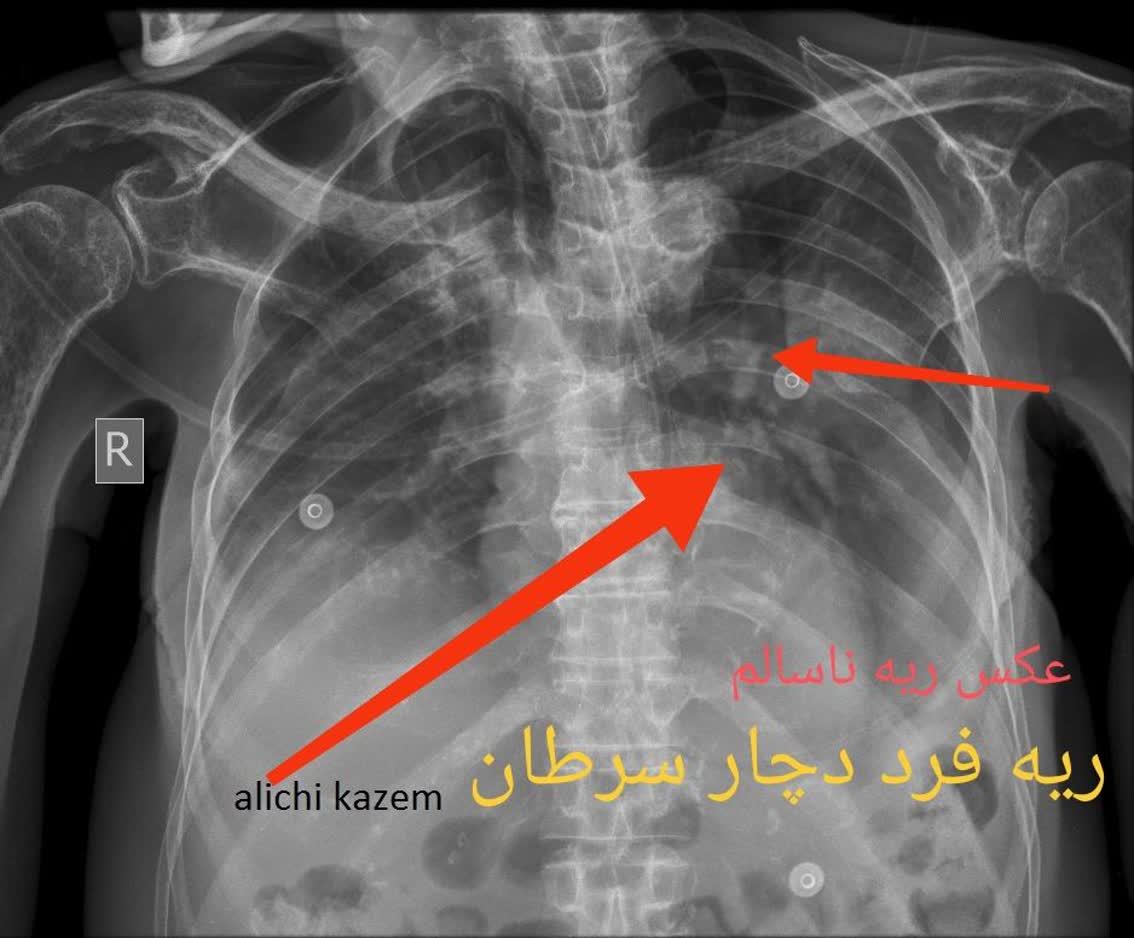

3. سرطان ریه: سرطان ریه یکی از بخشهای مهم سرطان است و ممکن است در افرادی که سیگار میکنند یا به عوامل ریسک دیگری تعریف شدهاند، پدیدار شود.

مقایسه عکس ریه سالم و ناسالم

در عکس ریه سالم و ناسالم، تفاوتها معمولاً با چشم غیرمسلح نیز مشهودند. ریه سالم تصویری یکنواخت و شفاف دارد، با خطوط ریوی طبیعی و بدون سایه یا توده. در مقابل، ریه ناسالم ممکن است سایههای غیرطبیعی، نواحی سفید شده (indicative of consolidation)، خطوط پررنگتر ناشی از فیبروز یا تودههای نامنظم را نمایش دهد. تشخیص این تفاوتها توسط پزشک رادیولوژیست، نیاز به تجربه و تجهیزات باکیفیت دارد، چیزی که در خدمات رادیولوژی ریه در منزل تهران و رادیولوژی ریه در منزل کرج فراهم شده است.